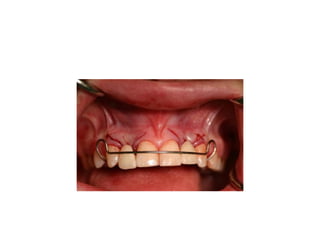

time of insertion

retainer has been modified

final crowns are delivered